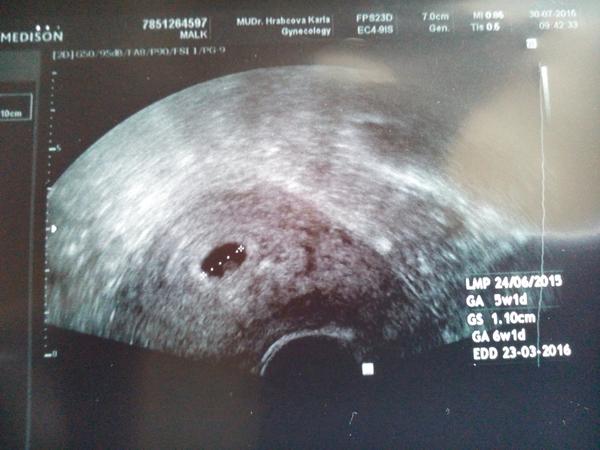

V 6tt je vidět jen gestační váček, měly jste to tak?

ahoj holky tak dneska jsem byla poprve na utz jsem 6 tt+ 0dni zatim byl videt jenom gestacni vacek 9mm,jinak nic meli jste to taky tak v 6 tydnu?vim ze tady jde o dny🙂ale hodne me rozhodila ,ze uz mi dala tehu prukazku,jen rekla tehotenstvi se vyviji dobre za dva tydny kontrola to uz bude srdicko prukazku muzeme dat uz dneska ..tohle jsem jeste nezazila,ze se dava tehu prukazka pred srdickem🙂vite jak se to rika,,aby se neco nezakriklo"

@viovka V 6tt jsem měla vidět vždycky jen dutinku, ani žloutkový váček nebyl. Za 14 dnů až 3 týdny už byl mrňous vidět včetně srdíčka.

Když jsem zjistila, že jsem těhu, tak jsem byla hned druhý den u gyn a byla jsem 5+2tt - t.č. byl vidět jen gestační váček(dutinka) bez žloutkového váčku. O tři týdny později v 8+2tt již bylo vidět tepající srdíčko.